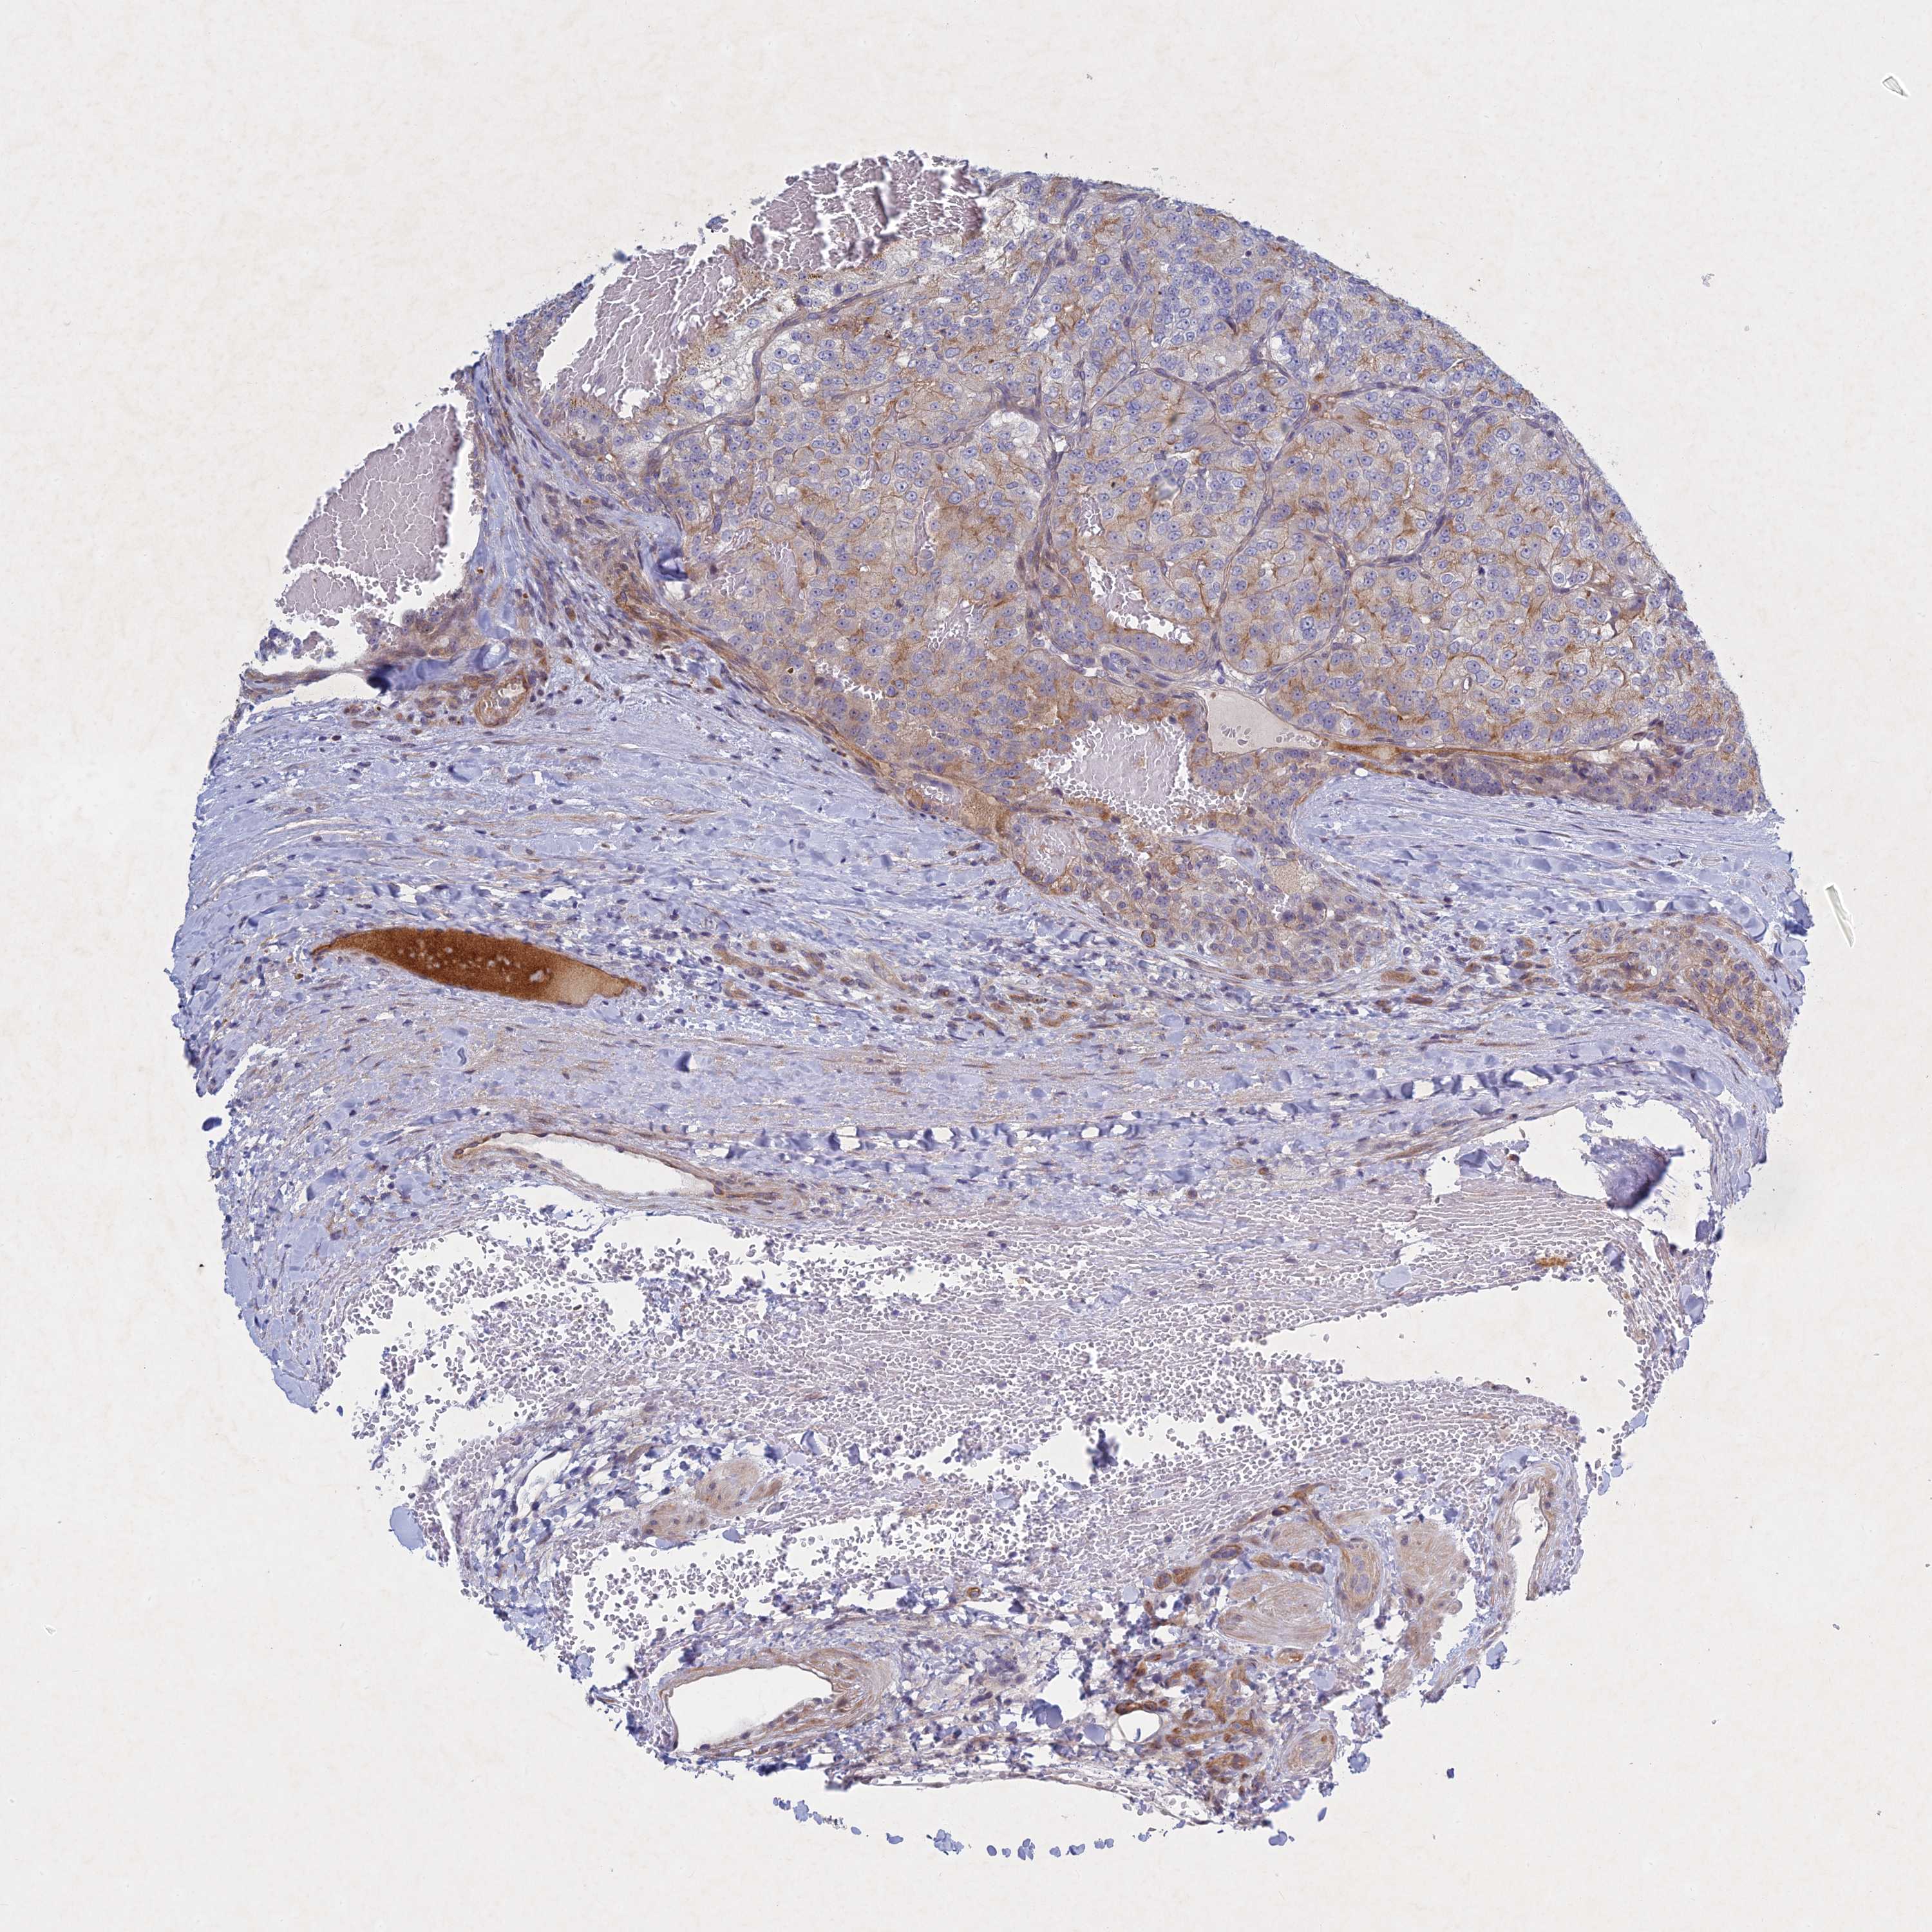

KIDNEY RENAL CLEAR CELL CARCINOMA (VALIDATION) - Interactive survival scatter ploti

The Survival Scatter plot shows the clinical status (i.e. dead or alive) for all individuals in the patient cohort, based on the same data that underlies the corresponding Kaplan-Meier plots. Patients that are alive at last time for follow-up are shown in blue and patients who have died during the study are shown in red.

The x-axis shows the expression levels (FPKM) of the investigated gene in the tumor tissue at the time of diagnosis. The y-axis shows the follow-up time after diagnosis (years). Both axes are complimented with kernel density curves demonstrating the data density over the axes. The top density plot shows the expression levels (FPKM) distribution among dead (red) and alive patients (blue). The right density plot shows the data density of the survived years of dead patients with high and low expression levels respectively, stratified using the cutoff indicated by the vertical dashed line through the Survival Scatter plot. This cutoff is automatically defined based on the FPKM cutoff that minimizes the p-score. The cutoff can be changed by dragging the vertical line or by entering a cutoff value in the square labeled "Current cut-off".

Under the Survival Scatter plot the p-score landscape (black curve; left axis) is shown together with dead median separation (red curve; right axis). Dead median separation is the difference in median mRNA expression between patients who have died with high and low expression, respectively. It is calculated as follows: median FPKM expression of dead patients with high expression - median FPKM expression of dead patients with low expression. This is intended to aid the user in visually exploring custom cutoffs and the associated p-scores and dead median separation.

Individual patient data is displayed and can be filtered by clicking on one or more of the category buttons on the top of the page. Categories describing expression level and patient information include: high, low, alive, dead, female, male and tumor stages. The scale of the x-axis can be toggled between linear and log-scale by clicking on the "x log" button. Mouse-over function shows TCGA ID, patient information and mRNA expression (FPKM) for each patient.

& Survival analysisi

Kaplan-Meier plots summarize results from analysis of correlation between mRNA expression level and patient survival. Patients were divided based on level of expression into one of the two groups "low" (under cut off) or "high" (over cut off). X-axis shows time for survival (years) and y-axis shows the probability of survival, where 1.0 corresponds to 100 percent.

PTHLH is not prognostic in Kidney Renal Clear Cell Carcinoma (validation)

Best expression cut offi

Based on the FPKM value of each gene, patients were classified into two groups and association between prognosis (survival) and gene expression (FPKM) was examined. The best expression cut-off refers the FPKM value that yields maximal difference with regard to survival between the two groups at the lowest log-rank P-value. Best expression cut-off was selected based on survival analysis .

When clicking on this number, the vertical dashed line indicating cut-off, the interactive survival plot, and the Kaplan-Meier curve will be adjusted to show results based on the best expression cut-off.

: 76.19

TCGA RNA samplesi

RNA-seq data is reported as average FPKM (number Fragments Per Kilobase of exon per Million reads), generated by the The Cancer Genome Atlas (TCGA) .

Normal distribution across the dataset is visualized with box plots, shown as median and 25th and 75th percentiles. Points are displayed as outliers if they are above or below 1.5 times the interquartile range. FPKM values of the individual samples are presented next to the box plot.

Average pTPM 114.7

Number of samples 100